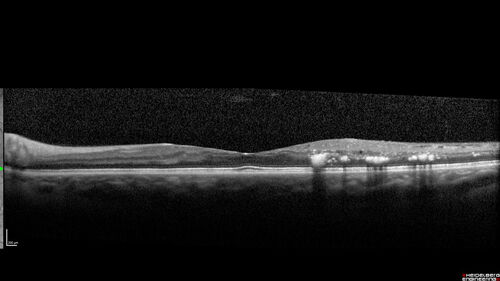

Macular ischemia left eye in type I diabetic (enlarged foveal avascular zone)

29 year old female with type I diabetes since age 5. Left eye has enlarged FAZ with vision of 20/20 OD and 20/60 OS. Both eyes have CSME. The left eye did have focal laser